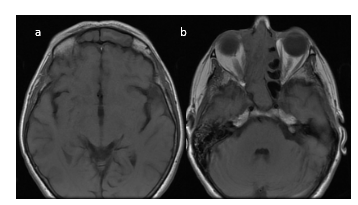

En RM, secuencia en T1, la lesión se observa hipo-isointensa y se proyecta desde orificio nasal hasta Cavum y coana, con aspecto de lesión solida expansiva ubicada sobre seno maxilar derecho que se extiende alrededor de la pared interna del seno nasal hacia la fosa nasal homolateral y se proyecta hasta senos frontales y presenta erosión de la lámina papirácea (Figura 5 – 6 – 7).

En secuencia T2 sin contraste, la lesión presenta áreas hiperintensas y de baja señal, determinando marcado desplazamiento del tabique nasal y oblitera trompa de Eustaquio derecha, con ocupación de celdillas mastoideas y oído medio homolaterales (Figura 8–9-10).

En RM con contraste la lesión presenta un realce intenso al gadolinio (Figura 11 – 12 – 13).